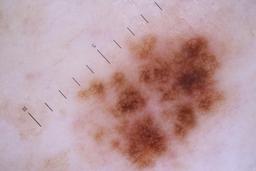

ISIC_6742970

- Sydney Melanoma Diagnostic Center at Royal Prince Alfred Hospital, Pascale Guitera

- Challenge 2020: Training

Clinical

| Field | Value |

|---|---|

| acquisition_day | 91 |

| age_approx | 75 |

| anatom_site_1 | Trunk |

| anatom_site_2 | Posterior trunk |

| concomitant_biopsy | False |

| diagnosis_1 | Benign |

| diagnosis_confirm_type | serial imaging showing no change |

| fitzpatrick_skin_type | I |

| image_type | dermoscopic |

| lesion_id | IL_7403129 |

| patient_id | IP_4261345 |

| sex | male |